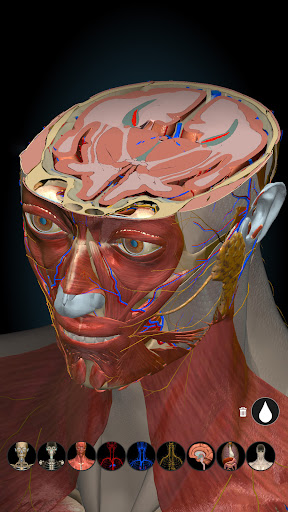

★ Remove structures to reveal the anatomical structures below them.

★ Switch on/off different anatomy systems

★ Central nervous system

★ Peripheral nervous system

★ Sense organs